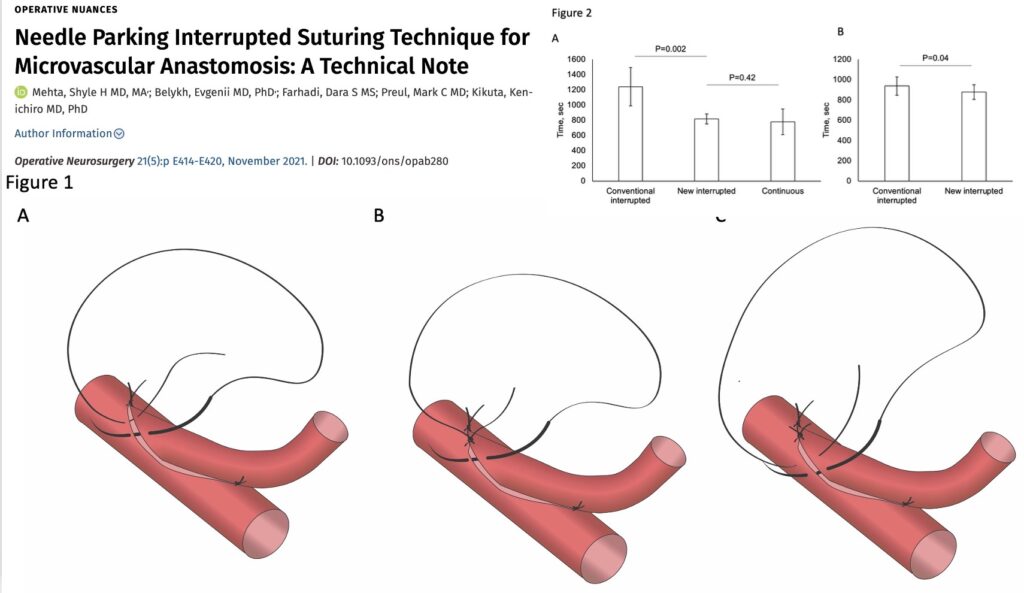

次の針はまち針のように通してあり、しかも糸は常に繋がっていますので、針は無くなりません(Needle parking mehtod)